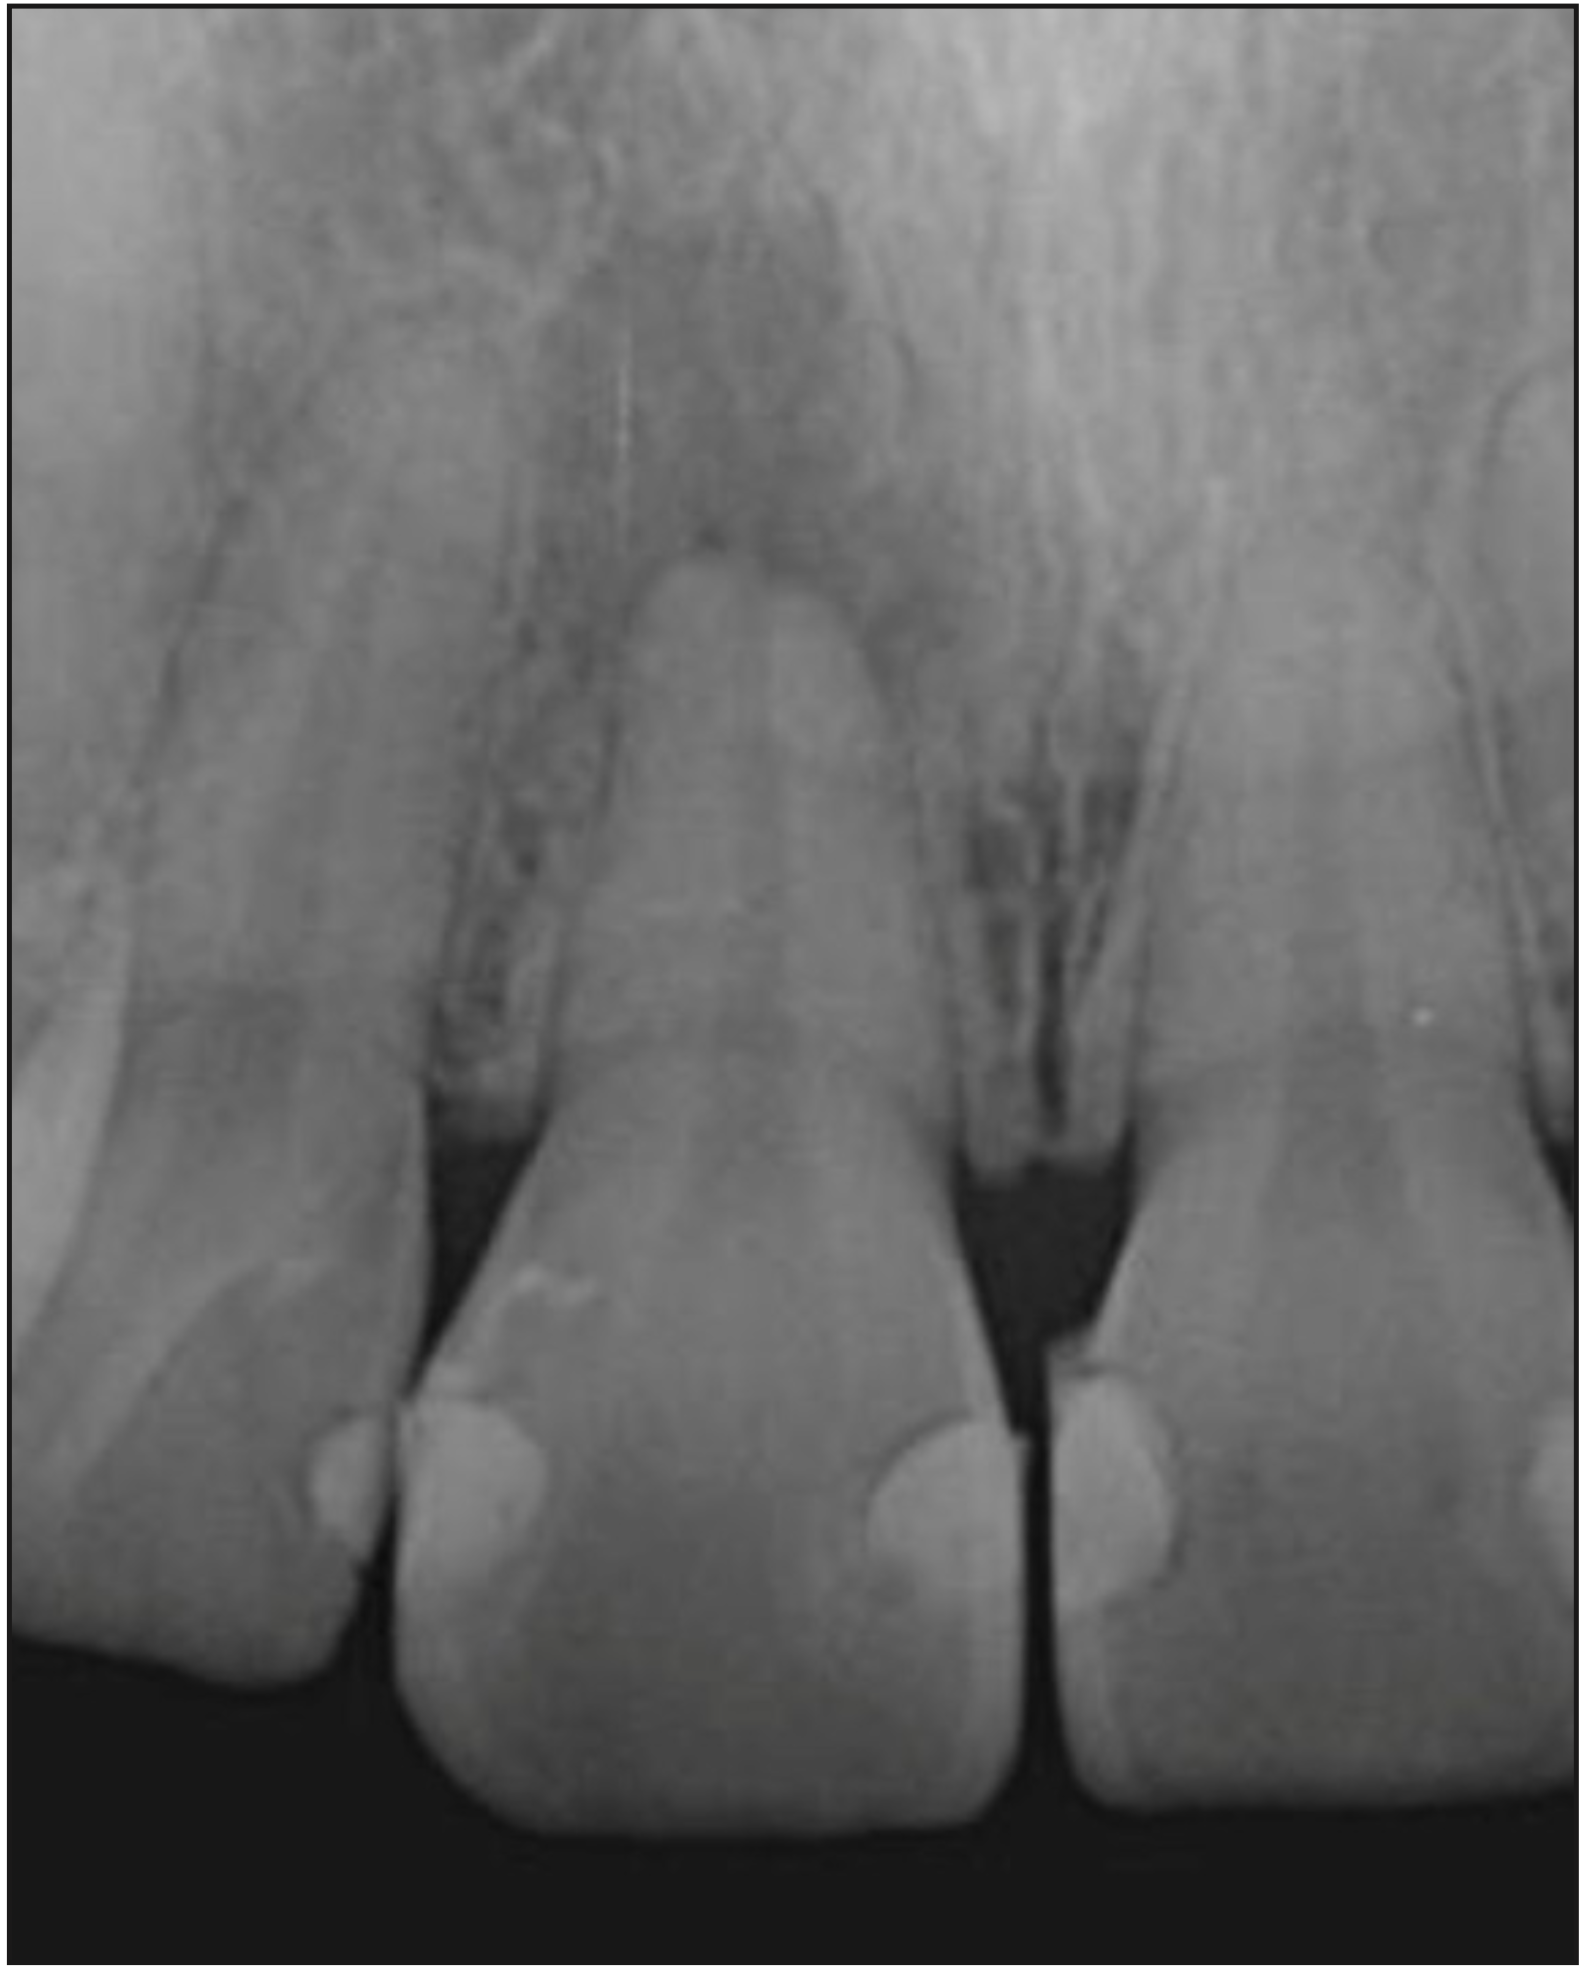

En el examen radiológico se observa una lesión osteolítica apical circunscrita de tamaño 5x8 mm. (Figura 1); además, se decidió complementar con tomografía computarizada de haz cónico debido a la movilidad presentada (Figura 2) en la que se logró visualizar la lesión en forma más precisa entregando una medida de aproximadamente 5x8,5x5mm, con compromiso de la tabla ósea vestibular, manteniendo una banda de tejido óseo a nivel cervical vestibular de entre 3,51 a 4,36 mm y mantención de la tabla palatina.

Figura 1. Radiografía retroalveolar de diagnóstico del diente

1.1. Canal radicular amplio, con remodelado. Se observa lesión osteolítica apical extensa circunscrita.